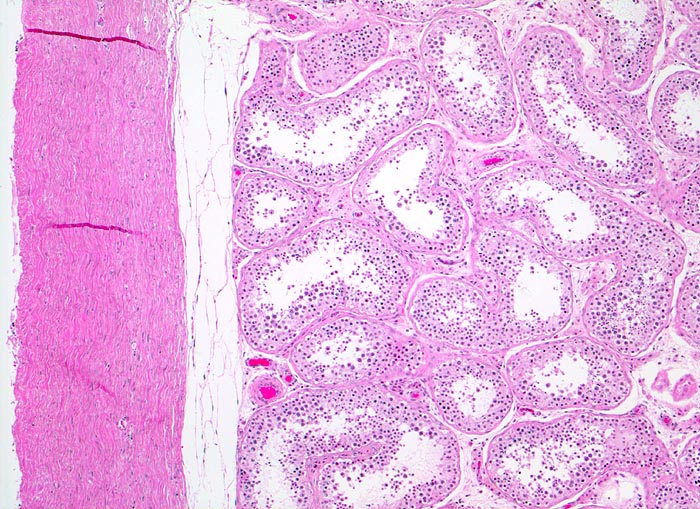

Makroskopisch imponieren Seminome als gut begrenzte weiche crèmefarbene Knoten oder diffuses Intiltrat. Mikroskopisch findet sich eine uniforme Population grosser Zellen mit prominentem zentralem Nukleolus, welche durch schmale Bindegewebssepten voneinander getrennte Nester bilden. Ein leukozytäres Entzündungsinfiltrat, synzytiotrophoblastäre Riesenzellen und Mikroverkalkungen können zusätzlich vorhanden sein. Gelegentlich induziert der Tumor eine ausgeprägte granulomatöse Entzündung. Dies kann zur Fehldiganose einer granulomatösen Orchitis führen.

• Scharf begrenzter Tumorknoten mit eosinophilen Nekrosearealen.

• Unterschiedlich breite solide Tumorzellstränge aus monomorphen Zellen mit grossen hyperchromatischen Kernen und einem solitären zentralen prominenten Nukleolus. Reichlich helles Zytoplasma mit scharfen Zellgrenzen.

• Schmale bindegewebige Septen mit Kapillaren und lymphoplasmazellulärem Entzündungsinfiltrat.

• Tubuläre Atrophie des angrenzenden Hodenparenchyms. Einige Hodentubuli enthalten stark atypische pleomorphe Keimzellen (Keimzellneoplasie in situ).